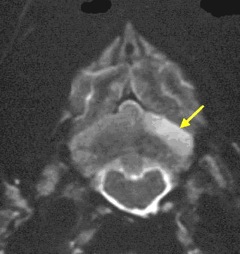

The only accurate way to diagnose an infarction is using magnetic resonance

imagine (MRI), and to a limited extent, computed tomography (CT), to obtain

scans of brain images. Early enough CT imaging should enable the veterinarian to

determine whether the infarct was caused by a burst blood vessel (hemorrhagic),

but MRI is the best device for identifying a shut down blood vessel (ischemic),

which will better determine the treatment protocol.

(The image at right is an MRI scan of a CKCS skull, showing a wedge-shaped cerebellar infarct at lower right of the brain. Image from The Downs Veterinary Practice.)